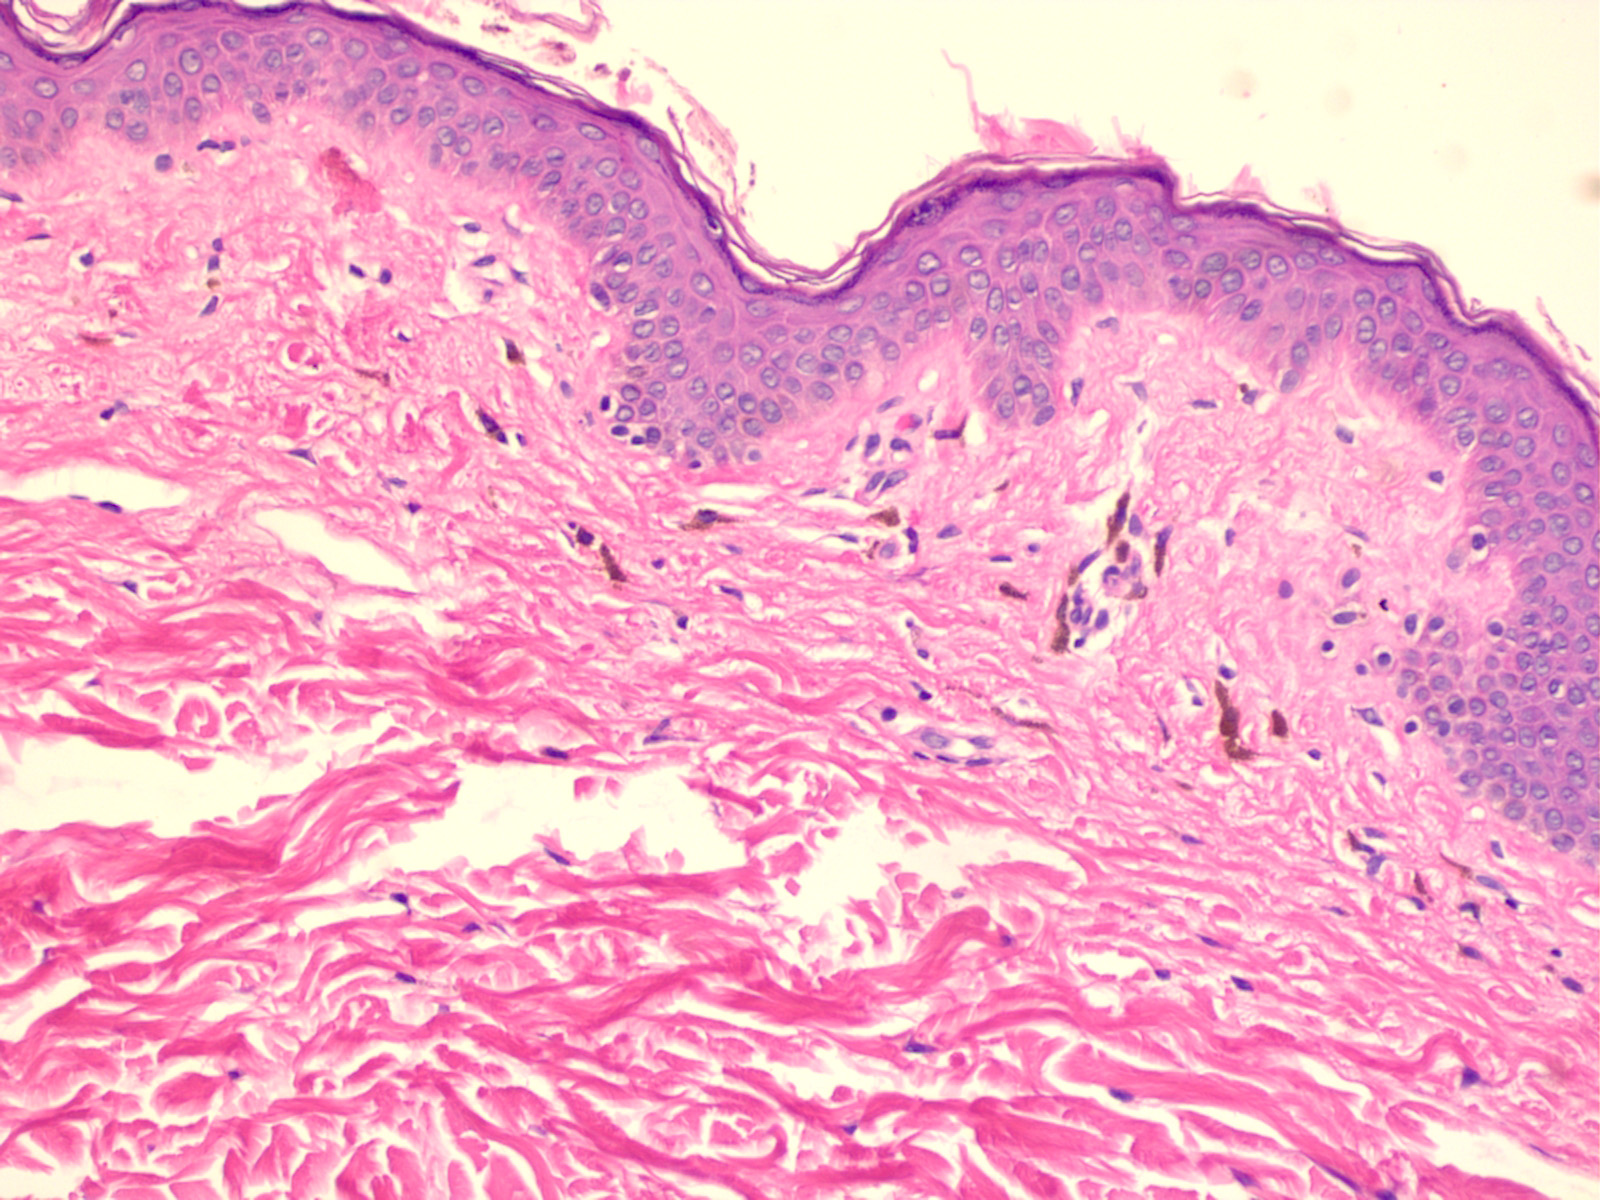

Superficial EAC has epidermal changes of parakeratosis and spongiosis, with a superficial perivascular infiltrate . Deep EAC lacks epidermal damage and has intense lymphohistiocytic cuffing about both the superficial and deep vessels . There is minimal papillary dermal edema and no spongiosis. One should search carefully for mucin as a clue to lupus erythematosus.